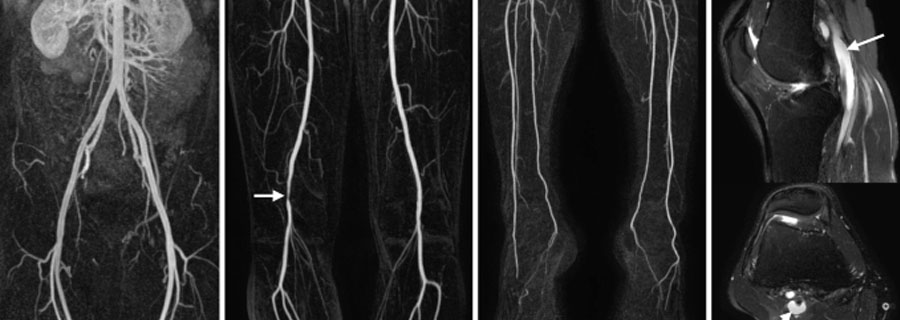

Noninvasive angiography of peripheral arteries is a medical imaging technique used to visualize and assess the blood vessels in the peripheral parts of the body, such as the arms, legs, and neck, without the need for invasive procedures like catheterization. It is primarily employed to diagnose conditions related to peripheral arterial disease (PAD) and evaluate blood flow in these areas.

• Magnetic Resonance Angiography (MRA): MRA uses a magnetic field and radio waves to create detailed images of blood vessels. It is particularly useful for visualizing larger vessels and is less reliant on contrast agents than computed tomography (CT) angiography.

• Computed Tomography Angiography (CTA): CTA involves the injection of a contrast dye into a vein to enhance the visibility of blood vessels while performing a CT scan. It provides high-resolution images of peripheral arteries and can identify arterial stenosis or occlusions.